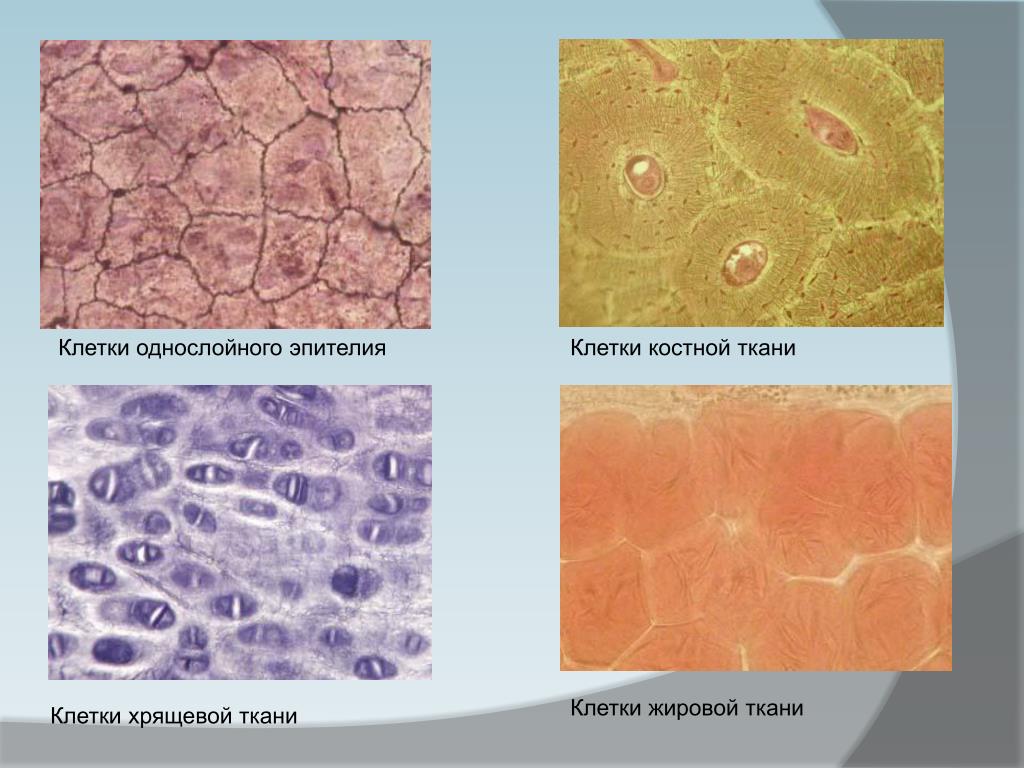

Структура грубоволокнистой костной ткани: наглядные примеры